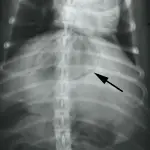

Emphysematous cholecystitis is a necrotizing inflammation of the gallbladder caused by a gas-forming bacterial infection that severely damages the gallbladder wall. It is usually accompanied by cholangiohepatitis, which can occur because of an ascending infection from the small bowel or by hematogenous spread of an infection occurring elsewhere in the body. Clinical signs include gas in the gallbladder as shown in the accompanying radiograph (arrow), fever, decreased appetite, occasional vomiting, and discomfort of the anterior abdomen. A ruptured gallbladder will magnify the extent of clinical illness. Treatment entails patient stabilization with antibiotics and intravenous fluids and surgical removal of the infected gallbladder, especially when it is grossly discolored as shown in the photo. A reported mortality rate of 39% is most likely due to delayed diagnosis.

A radiograph shows a lateral view of a dog's thorax, highlighting a round, radiopaque mass in the abdomen indicated by an arrow. The surrounding structures, including the ribs and vertebrae, are clearly visible, providing context for the mass's location.